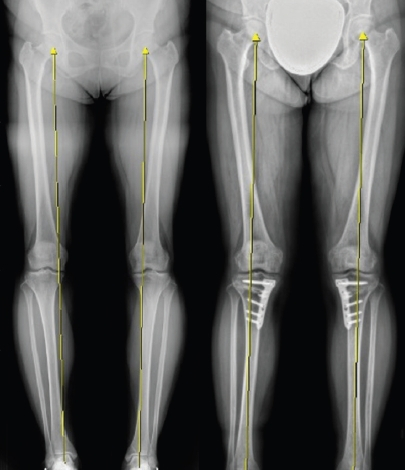

휜다리 교정술(근위경골절골술) 수술 전·후 사진. [강남제이에스병원]

따라서 이식된 줄기세포가 제대로 활성화될 수 있도록 무릎 관절의 하중을 적절히 분산시켜주는 ‘O자 변형 교정술(근위경골절골술, HTO)’이 반드시 선행되어야 한다는 것이 전문가들의 의견이다.

O자 변형 교정술은 무릎 아래뼈인 경골을 절골하여 무릎의 체중 부하선을 정상 위치로 이동시키는 정밀한 수술 방법이다. 뼈의 각도를 세밀하게 조절하여 무릎 안쪽보다 바깥쪽 연골을 더 많이 사용하도록 유도하는 기술로, 동시에 줄기세포 이식술로 인한 연골 재생 효과를 극대화할 수 있다.